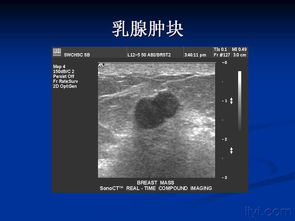

超聲診斷屬于醫(yī)學影像學診斷,它不同于病理組織學診斷,超聲診斷的結(jié)論根據(jù)綜合分析和影像的可信程度對結(jié)論進行較為肯定、可能不確定等層面的分級,并加以描述,定位診斷,病變解剖部位或器官組織的定位,確定某一器官的哪一部位有異常。

超聲對于病變的解剖部位或器官組織定位的診斷有比較高度的準確性,如心臟的瓣膜、肝臟的外葉上段,腎的下級或者上級等等。病變特征的診斷區(qū)分為彌漫性或局限性,囊性、實性或混合型。

超聲對病變物理性質(zhì)的判斷通常也是非常準確的。良性或惡性的診斷,只有在具有高度特異性的超聲表現(xiàn)的情況下,通過綜合判斷超聲才可以提示肯定而明確的診斷,如膽囊結(jié)石、死胎、肝囊腫等等。

必須強調(diào)的是超聲影像診斷不是病理組織學的診斷,由于大多數(shù)疾病的超聲表現(xiàn)是非特異性的,只能結(jié)合病史綜合分析,提示某一或某些疾病的可能性,所以在報告單中可以出現(xiàn)如甲狀腺左葉低回聲結(jié)節(jié),性質(zhì)待定這樣的結(jié)論。這時大夫會提出進一步的診斷建議,如穿刺活檢、CT掃查或者是甲狀腺功能檢查等等。